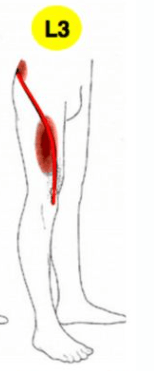

(臀中肌的傳導痛主要坐落在臀部外側往下延伸,但有些人會因為影響到梨狀肌導致薦髂關節與梨狀肌接到大轉子的地方也在痛)

這種疼痛方式會很像壓迫到第三節神經根的疼痛,所以在臨床上需要做更詳細的理學檢查評估,來區分到底是哪邊的問題。